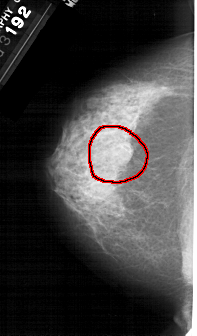

FILE: A_1396_1.LEFT_MLO.OVERLAY

TOTAL_ABNORMALITIES 1

ABNORMALITY 1

LESION_TYPE MASS SHAPE ROUND MARGINS OBSCURED

ASSESSMENT 4

SUBTLETY 3

PATHOLOGY BENIGN

TOTAL_OUTLINES 1

BOUNDARY